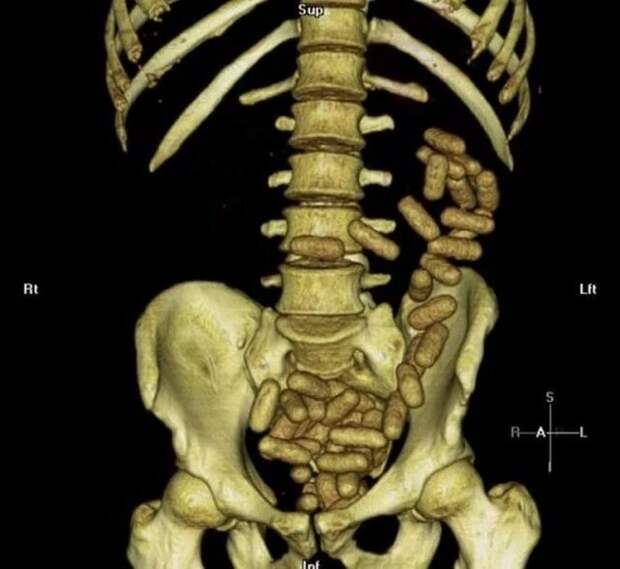

Кровеносные сосуды в пальце  Компьютерная томография человека, который вез внутри себя контрабанду

Компьютерная томография человека, который вез внутри себя контрабанду  Алкогольная атрофия мозга